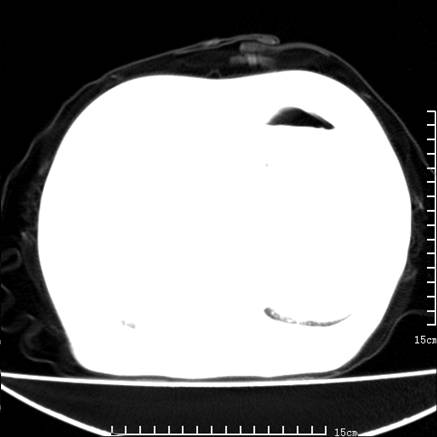

女,王某,58岁,咳嗽三个月余,基层医院二个月前诊为肺结核,用抗结核药二个月无明显疗效。

心包积液致肺瘀血.右侧周围型肺癌伴肺内转移,中间裂积液,叶间胸膜肥厚.右上肺大泡,右侧胸膜肥厚.

双肺继发型tb,心功能不全并肺淤血、心包、双侧叶间裂积液,肺大泡,右下胸膜肥厚钙化。